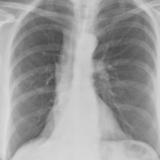

Gallery Lobar Collapse

Lobar Collapse